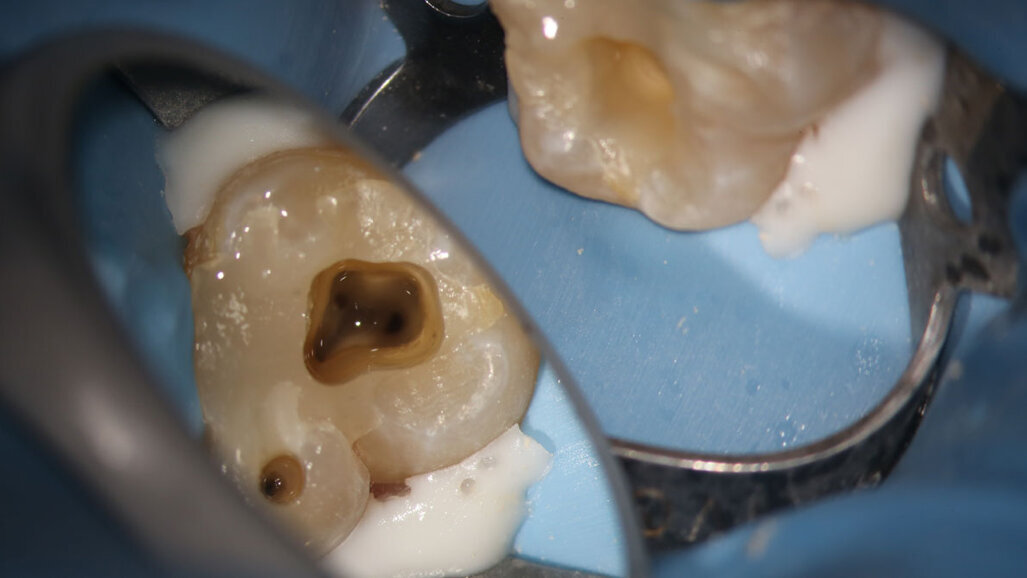

Fig. 17a: Case assisted with CBCT to determine anatomy pre-operatively. Note the multiple cross sections moving apically and the correlation to the 2-D view. Note also the conservative taper in relation to the root width. (Courtesy of Dr. Brett Gilbert)

Fig. 17b: Case assisted with CBCT to determine anatomy pre-operatively. Note the multiple cross sections moving apically and the correlation to the 2-D view. Note also the conservative taper in relation to the root width. (Courtesy of Dr. Brett Gilbert)

Fig. 17c: Case assisted with CBCT to determine anatomy pre-operatively. Note the multiple cross sections moving apically and the correlation to the 2-D view. Note also the conservative taper in relation to the root width. (Courtesy of Dr. Brett Gilbert)

Fig. 17d: Case assisted with CBCT to determine anatomy pre-operatively. Note the multiple cross sections moving apically and the correlation to the 2-D view. Note also the conservative taper in relation to the root width. (Courtesy of Dr. Brett Gilbert)

Fig. 17e: Case assisted with CBCT to determine anatomy pre-operatively. Note the multiple cross sections moving apically and the correlation to the 2-D view. Note also the conservative taper in relation to the root width. (Courtesy of Dr. Brett Gilbert)

Fig. 17f: Case assisted with CBCT to determine anatomy pre-operatively. Note the multiple cross sections moving apically and the correlation to the 2-D view. Note also the conservative taper in relation to the root width. (Courtesy of Dr. Brett Gilbert)

Managing complex anatomy is much simpler if the clinician has a pre-operative road map. The CBCT provides the roadmap and the surgical microscope the lens (literally) through which to visualize the result. Aside from a relaxed patient who is profoundly numb, being able to visualize anatomy by taking a pre-operative (and possibly intra-operative) CBCT and using a surgical microscope during treatment have no substitutes. They are the current “Gold Standard” in that 3-D imaging shows the clinician the true reality of a clinical situation as opposed to the suggestion gained from a 2-D radiograph. Proper interpretation of imaging prior to and/or during endodontic treatment goes a long way in taking the “guesswork” out of identifying canal location and other anatomical complexities as the procedure unfolds. In a 2014 study by El Fayad and Johnson, it was determined that when having a pre-operative CBCT as compared to 2-D radiographs alone, the treatment plan was modified 62 percent of the time. This is a huge game changer to think that the information learned from 3-D imaging changed the plan of treatment over six times out of 10 (Fig. 4).[2]

Access should be big enough to allow visual and tactile control, but not so large as to structurally weaken the tooth. Only as much dentin as required to allow adequate cleaning and shaping should be removed, but no more with effort being expended to always debride the tissue from the pulp horns and other hidden anatomy within the coronal portion of the tooth. Neelakantan et al (2018) determined that orifice-directed dentin conservation access design (ninja access) had significantly compromised debridement of the pulp chamber. Therefore, common sense is the best guideline when access design is considered assuring that the pulp chamber and all pulp horns are debrided.[3]